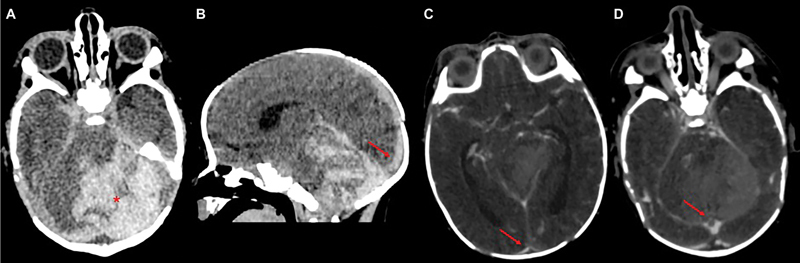

Study design: We report the case of a full-term neonate diagnosed with CSVT, highlighting the rationale for early anticoagulation with unfractionated heparin. A brief literature review supports our clinical decision-making, considering current evidence and expert consensus despite limited neonatal-specific guidelines.

Results: Heparin therapy was started shortly after diagnosis, without hemorrhagic complications. Neuroimaging showed complete thrombus resolution. The neonate had a normal neurological examination at discharge. Follow-up confirmed overall good clinical condition and showed mild axial hypotonia and convergent strabismus suggestive of cortical visual impairment.